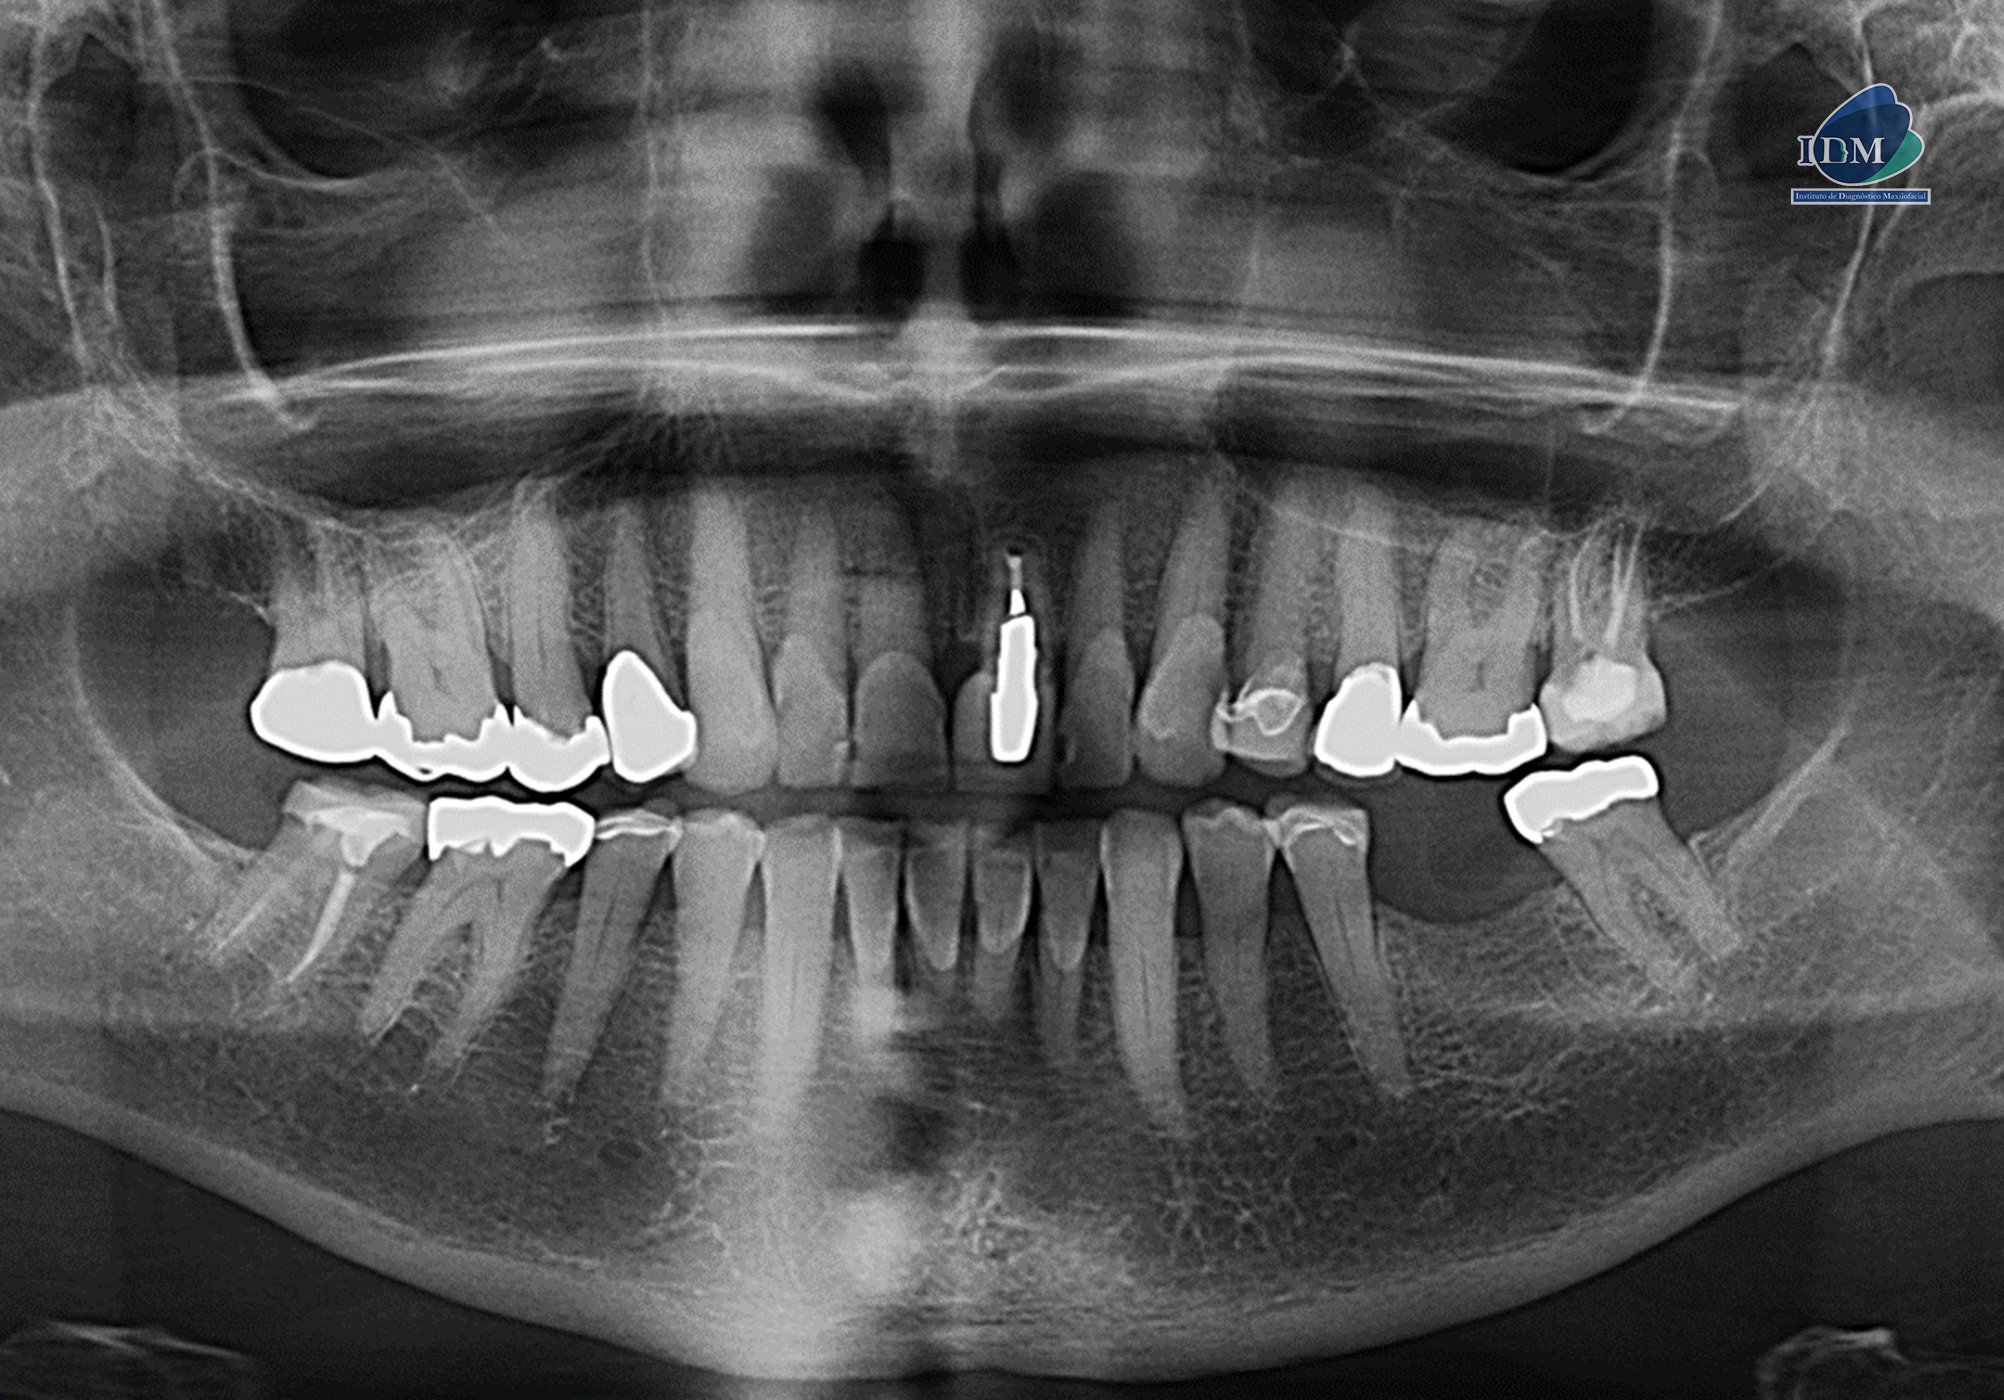

Radiografia Panorámica

A la evaluación de la radiografía panorámica se evidencia un aplanamiento severo del contorno de cóndilos mandibulares.